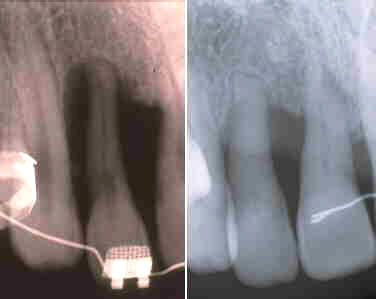

Estas imágenes ilustran la condición del soporte del hueso alveolar periodontal antes del tratamiento y 8 años después del tratamiento quirúrgico. El paciente ha mantenido una higiene oral excelente con citaciones cada 4 - 6 meses.